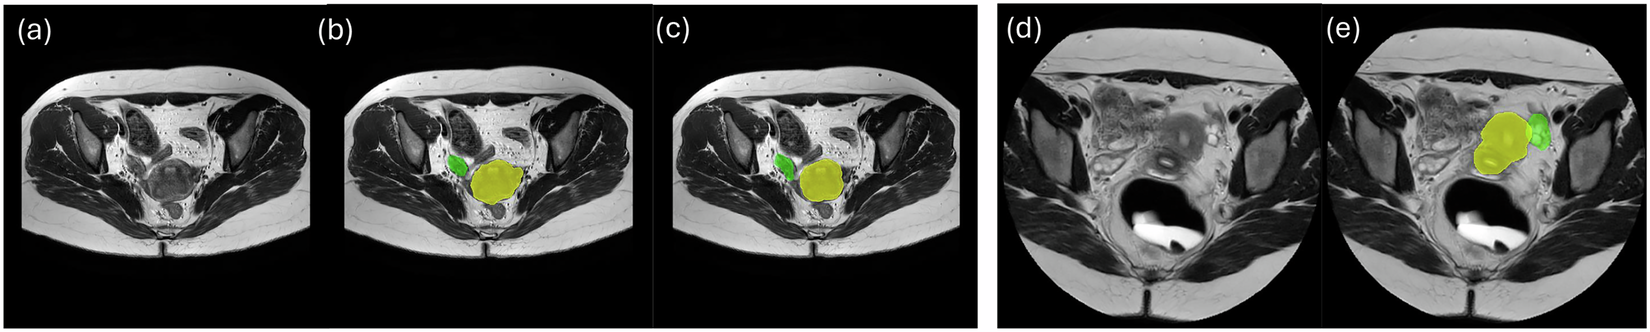

Fig. 1

From: A Multi-Modal Pelvic MRI Dataset for Deep Learning-Based Pelvic Organ Segmentation in Endometriosis

Examples of MRI scans for two Datasets. (a) T2-weighted MRI and (b,c) the corresponding uterus (yellow) and ovaries (green) labels from different raters for the first dataset. (d) T2-weighted MRI and (e) the corresponding uterus and ovaries labels for the second dataset.